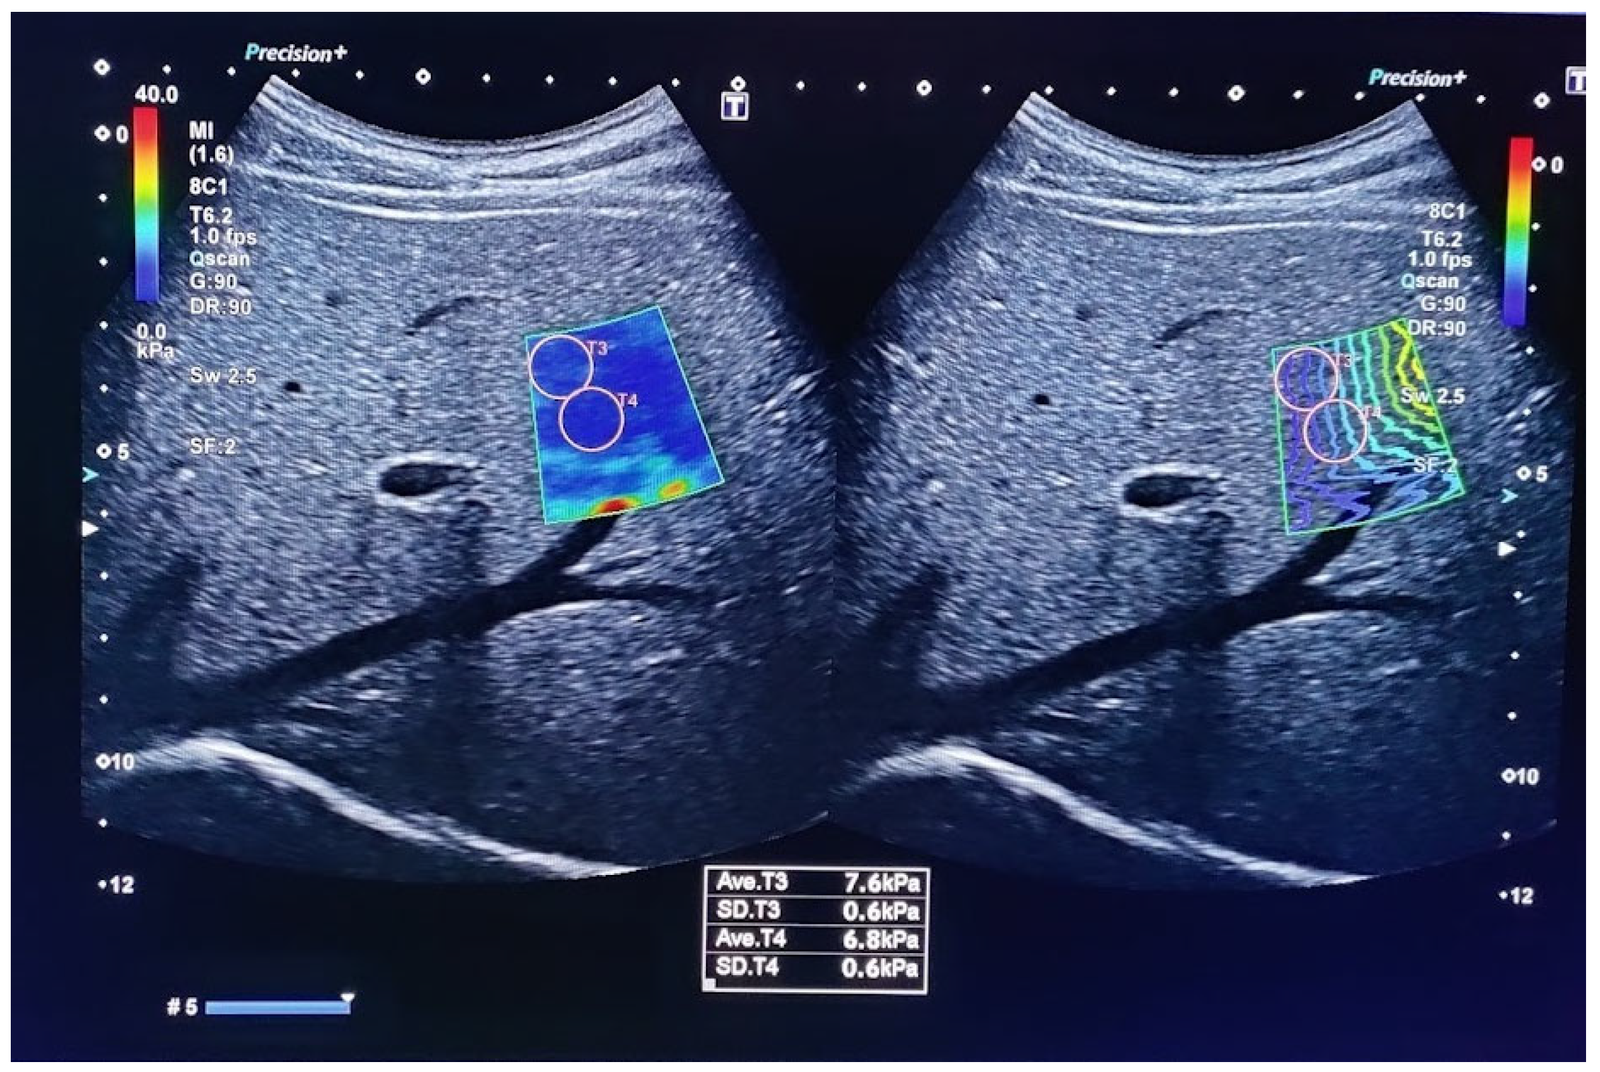

At Indianova Heart Center and Diagnostics, we provide Elastography, an advanced ultrasound-based imaging technique that measures the stiffness or elasticity of tissues. Unlike conventional ultrasound, which shows the structure of organs, elastography provides additional information about tissue properties, helping doctors detect abnormalities with greater accuracy.

This technique is especially valuable in the early detection and monitoring of conditions such as liver fibrosis, breast lesions, thyroid nodules, and other soft tissue abnormalities. By offering a non-invasive alternative to biopsy in many cases, elastography allows patients to receive quicker, safer, and more reliable diagnostic insights.